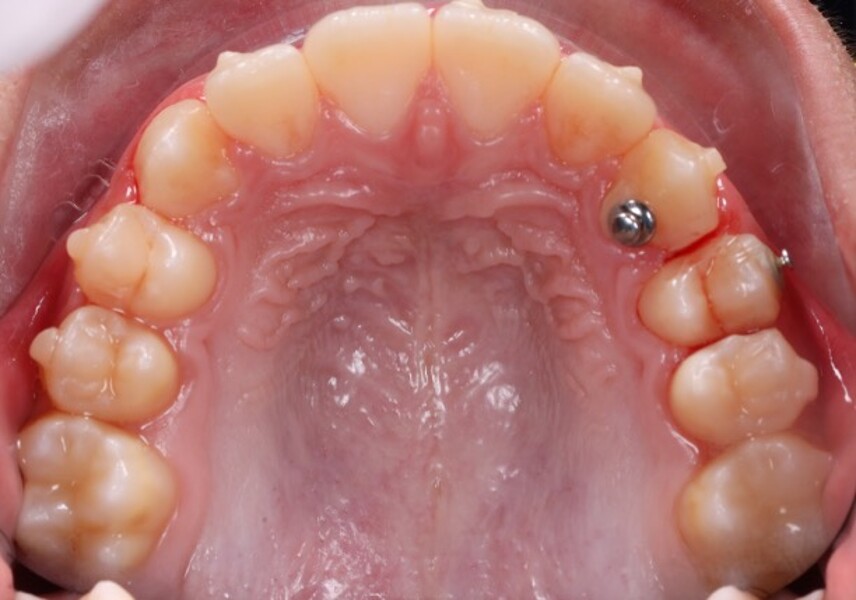

Figs. 2a–e: Pretreatment intra-oral photographs.

Figs. 6a–e: Intra-oral photographs after the first phase of treatment.

Clinical and radiographic evaluation revealed (Figs. 1–3):

a bilateral full-cusp Class II molar relationship;

an increased overjet of 11.7 mm;

a traumatic overbite of 7.2 mm; and

a narrow, collapsed V-shaped maxillary arch with a 2.0 mm midline deviation to the right.